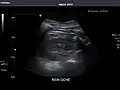

Kidneys: Right and left kidneys measure 11.5 cm and 12 cm in length respectively. No hydronephrosis. Small left lower pole kidney cyst.

Right kidney -